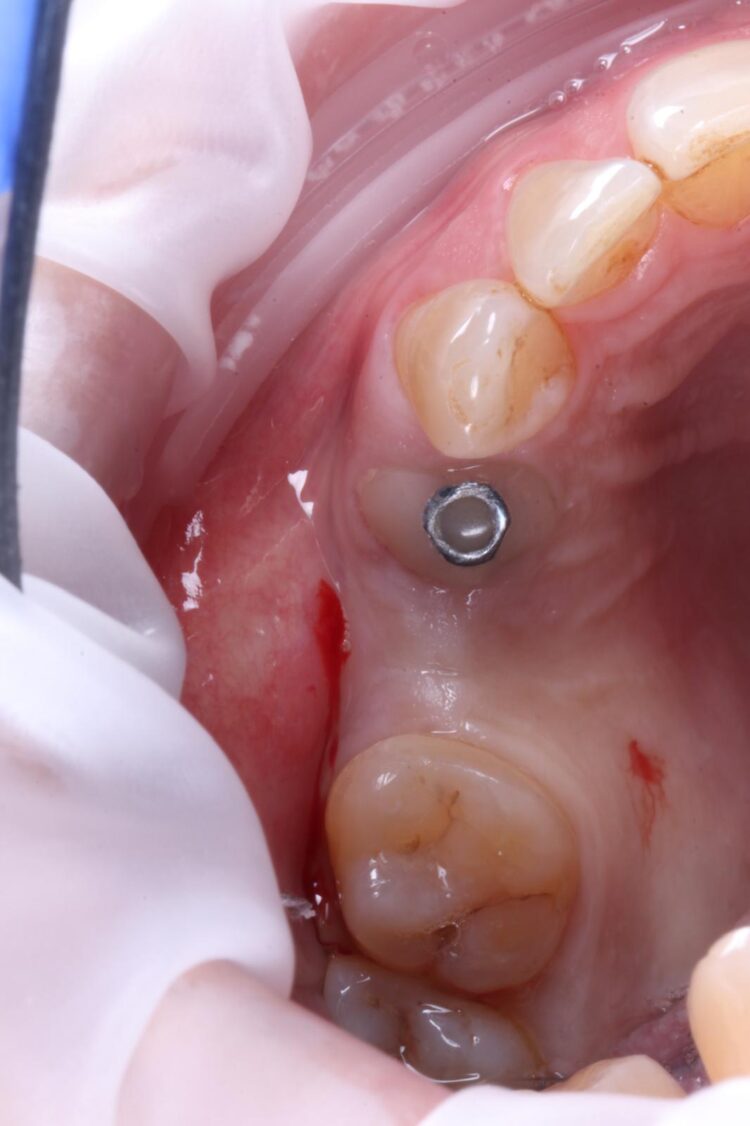

Consequently, the bone was contour-augmented, using MinerOss® Blend (BioHorizons Camlog), which provides a good combination of cortical and cancellous bone for efficient bone turnover and also maintains graft stability in the healing phase. The graft was held in place with a collagen membrane stabilised using resorbable sutures. The custom healing abutment is then placed and torqued (10Ncm) into the UL4 implant before the wound is approximated and sutured using a non-resorbable 6-0 Prolene suture.

An x-ray was taken immediately post-operatively to confirm that the temporary cylinder was seated correctly and wasn’t catching on the socket walls. This image also provided a reference for the custom healing abutment position and ensured that the bone graft material added to the jump gaps wasn’t preventing this abutment from fully seating.

The implant in the UL5 was uncovered 3 months later to reveal healthy tissues. Three weeks later the final scan was taken (using trios intra-oral scanner) for the fabrication of the definitive crowns. On the day of crown fits both abutments were removed and the crowns seated. Due to the UL4 site having a custom healing abutment, which had been supporting our ideal emergence profile, it was much easier to engage this restoration and seat within the already moulded soft tissues.